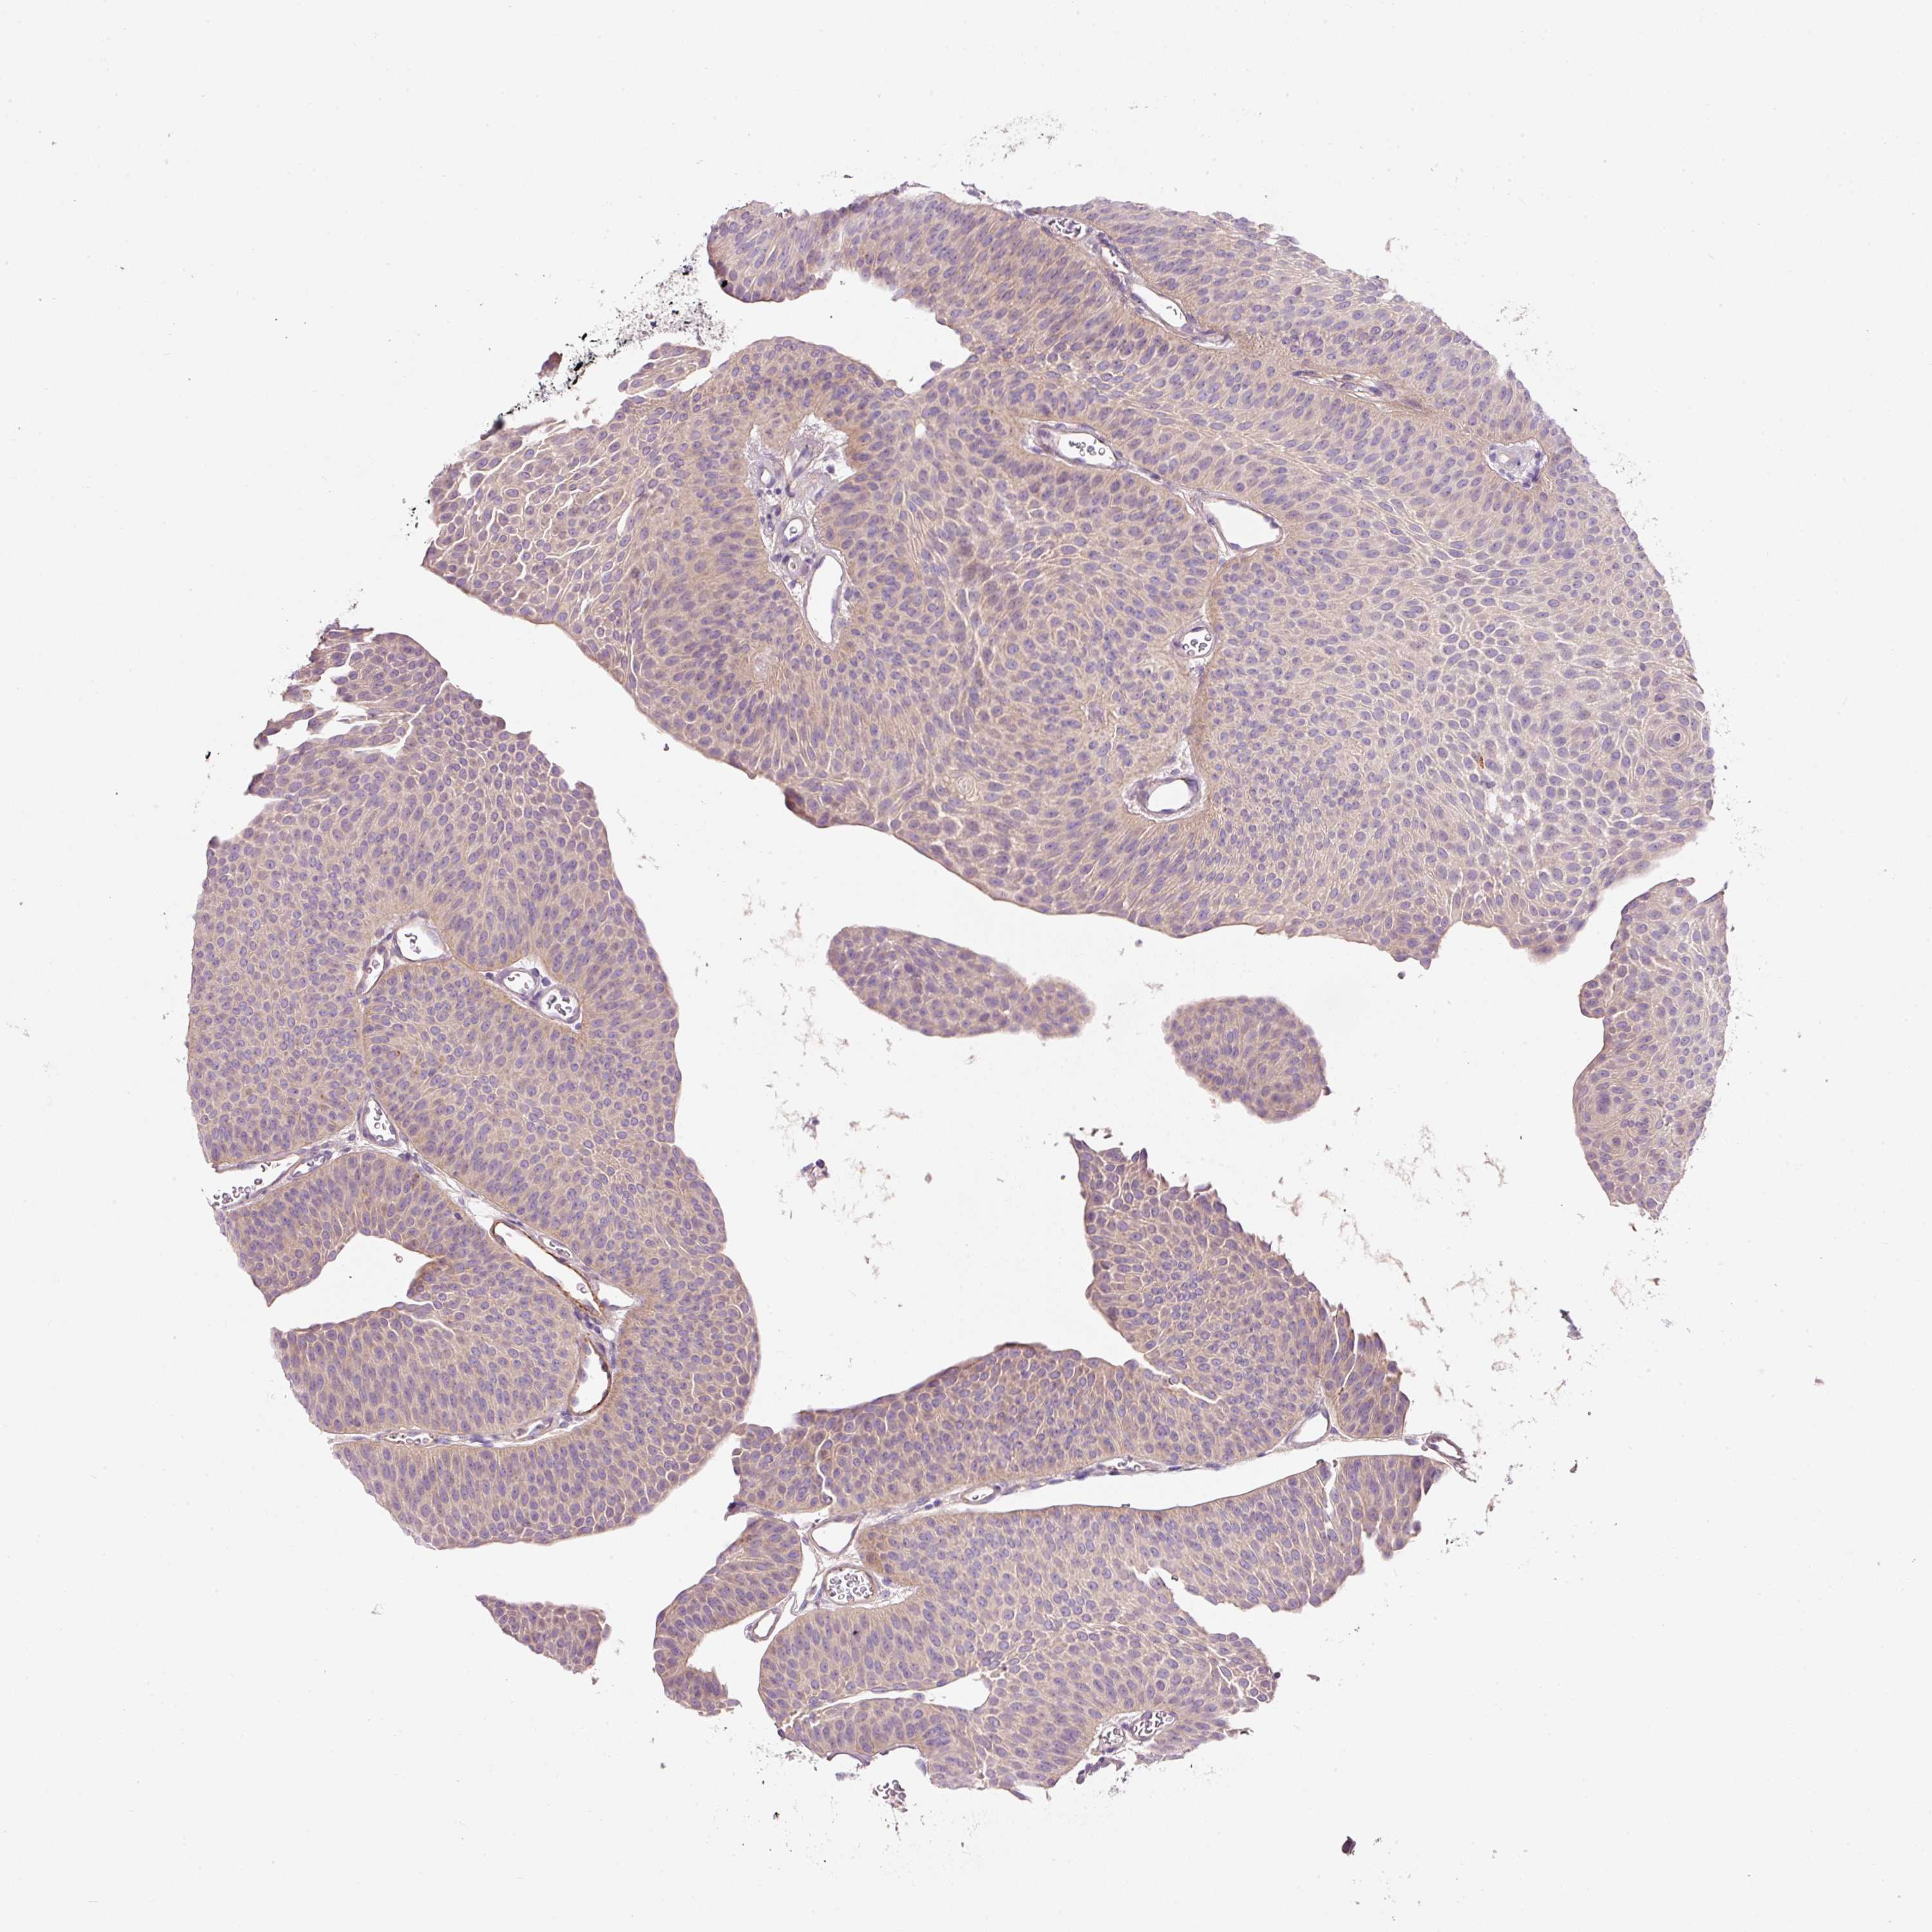

UROTHELIAL CANCER - Protein expressioni

A mouse-over function shows sample information and annotation data. Click on an image to view it in a full screen mode. Samples can be filtered based on level of antibody staining by selecting one or several of the following categories: high, medium, low and not detected. The assay and annotation is described here.

Antibody stainingi

Antibody staining in the annotated cell types in the current human tissue is reported as not detected, low, medium, or high, based on conventional immunohistochemistry profiling in selected tissues. This score is based on the combination of the staining intensity and fraction of stained cells.

Each image is clickable and will lead to virtual microscopy that enables deeper exploration of all samples and also displays staining intensity scores, fraction scores and subcellular localization as well as patient and tissue information for each sample.

Antibody HPA047368

Antibody CAB004577

Staining

High

Medium

Low

Not detected

Intensity

Strong

Moderate

Weak

Negative

Quantity

>75%

75%-25%

<25%

None

Location

Nuclear

Cytoplasmic/membranous

Cytoplasmic/membranous,nuclear

Urothelial carcinoma, High grade

Urothelial carcinoma, Low grade